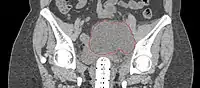

- Postoperative Lymphocele